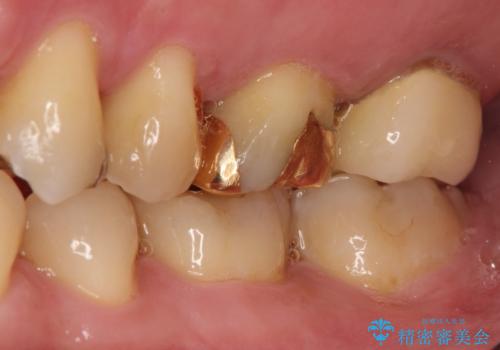

目立つ金歯を自然な色のオールセラミックへ

- 矯正の治療後に目立つ金歯を白くしたいとのことで治療することとなりました。

左上の奥歯に大きな金歯と、その後ろの歯が矯正治療用の仮歯が装着されていました。

これらの歯にオールセラミッククラウンを装着することとなりました。